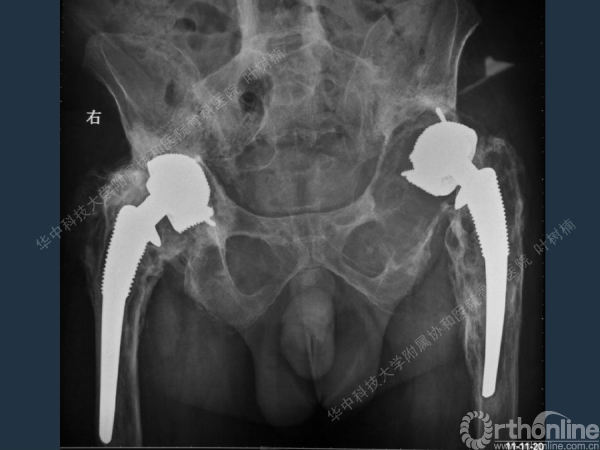

股骨侧翻修

髋臼缺损的处理